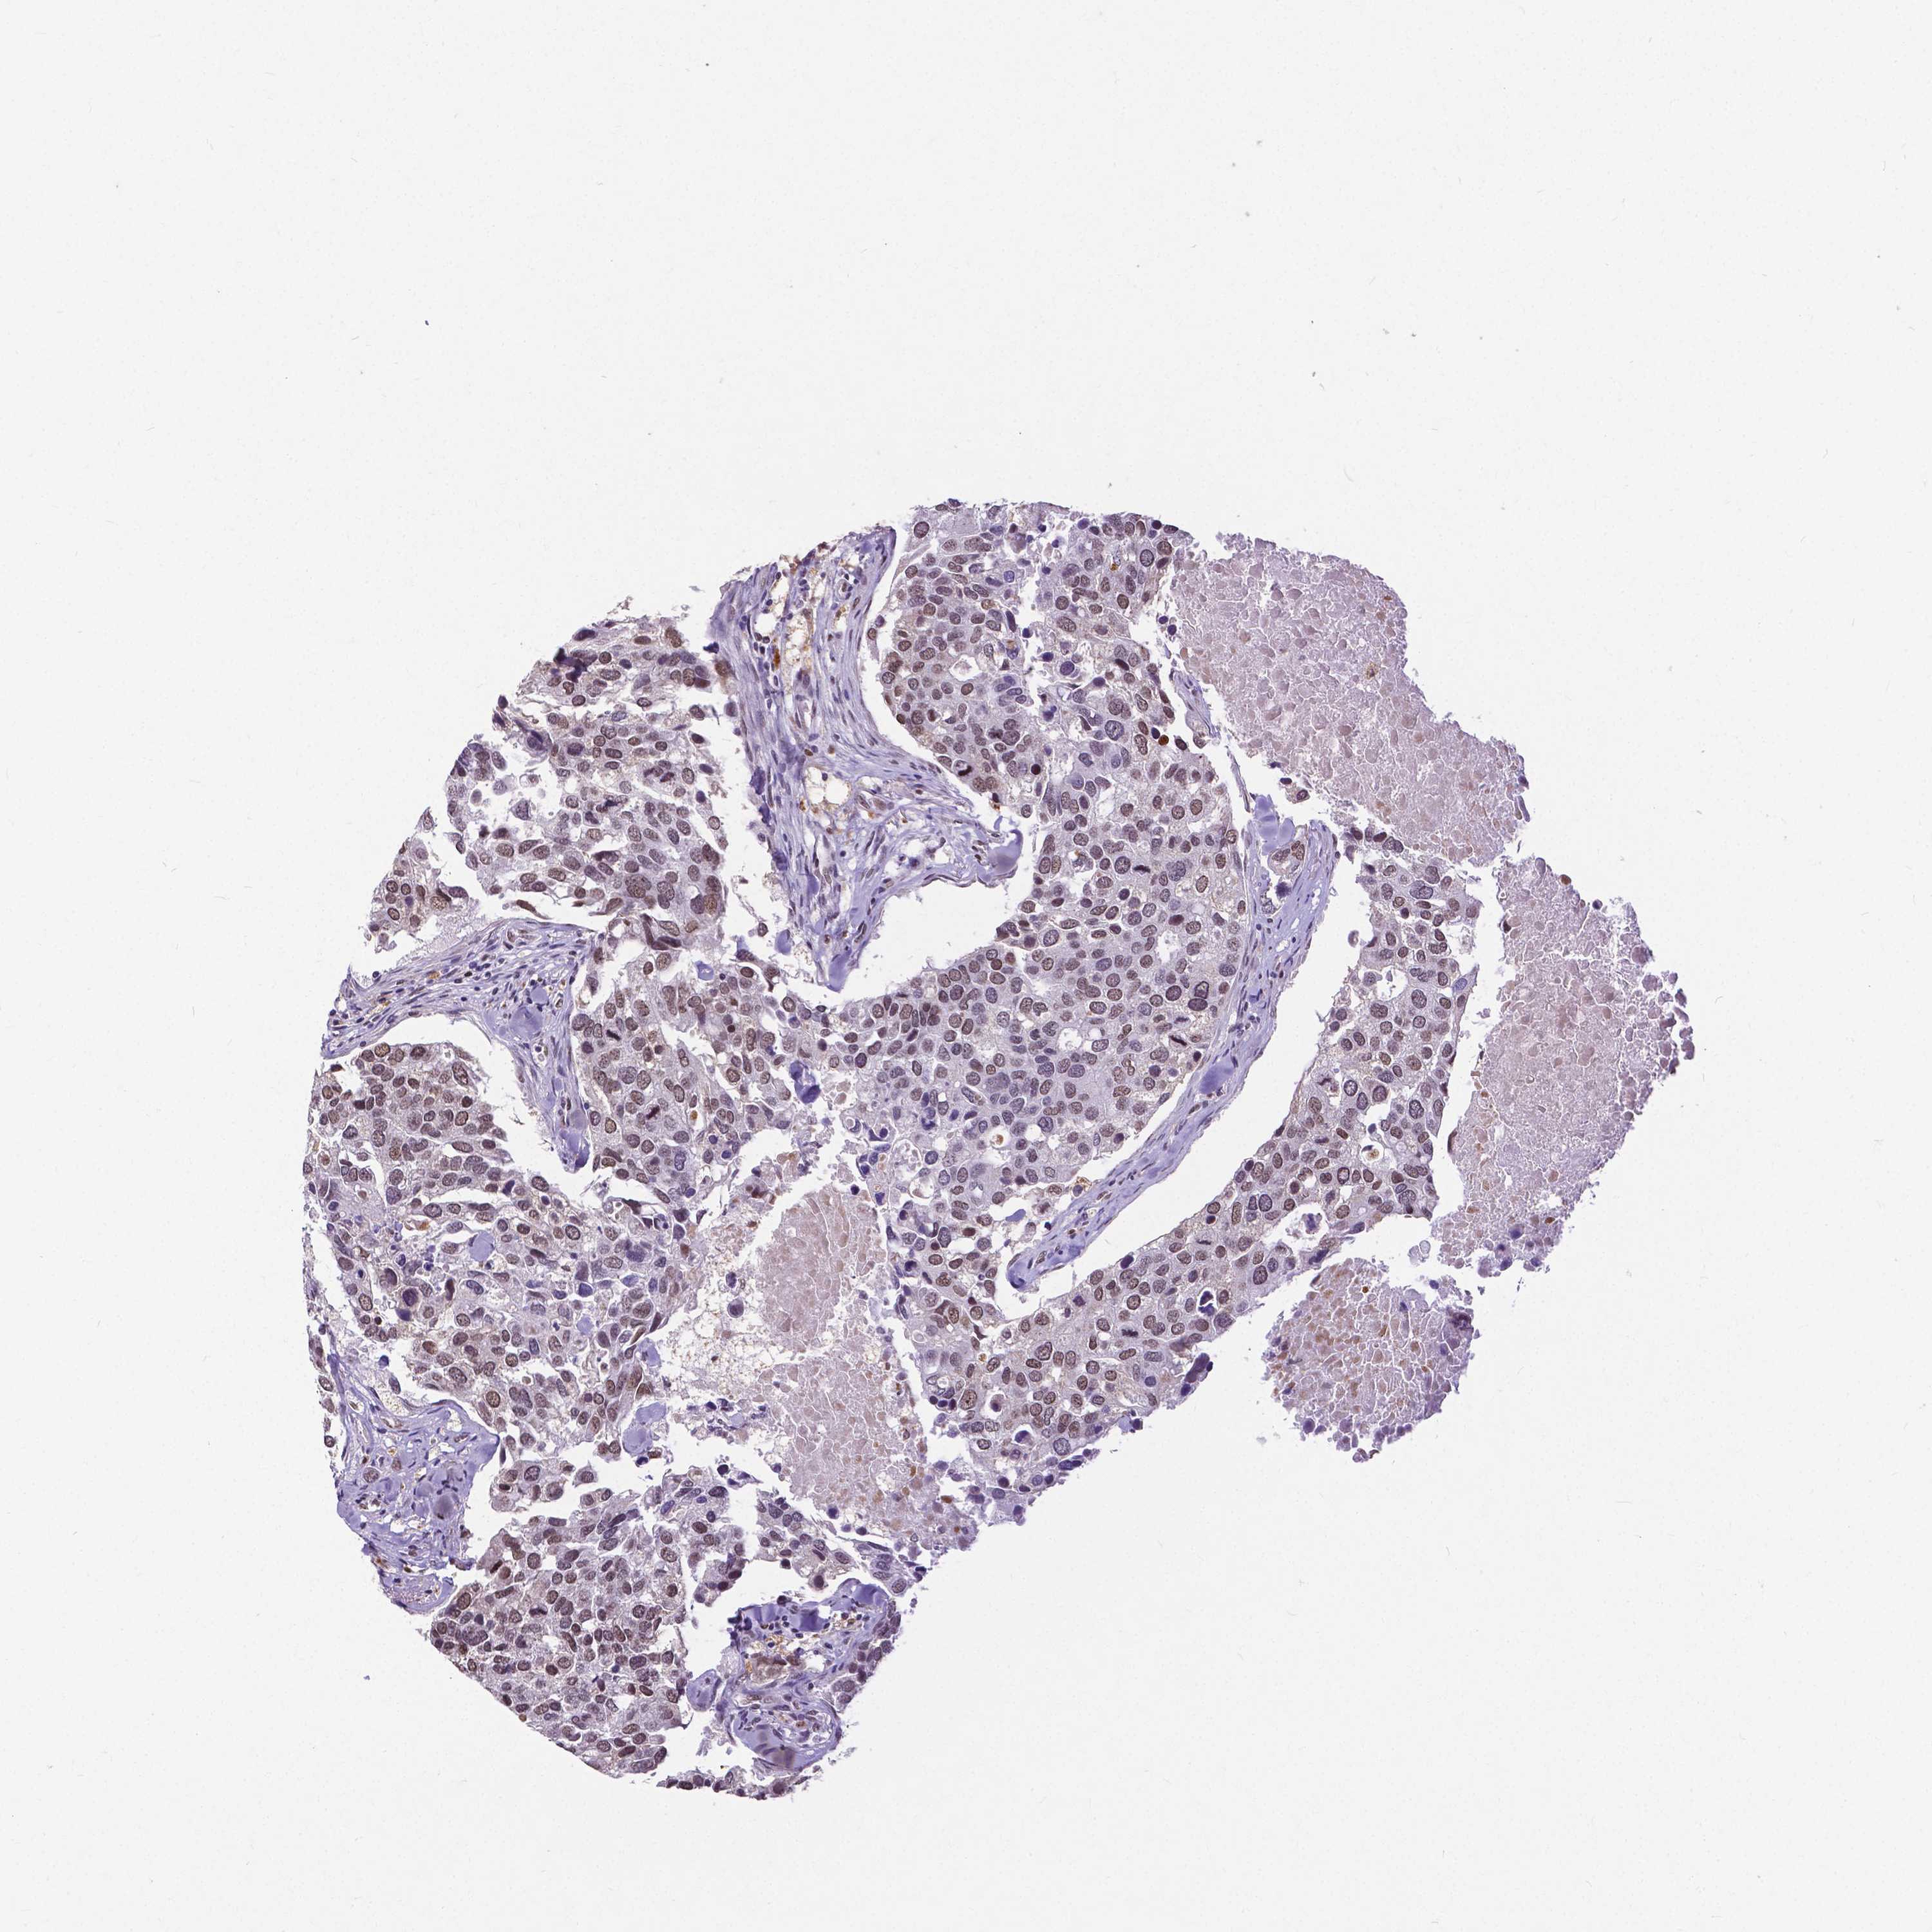

CANCER BREAST CANCER Show tissue menu

BRCA TCGA BRCA VALIDATION PROTEIN EXPRESSION